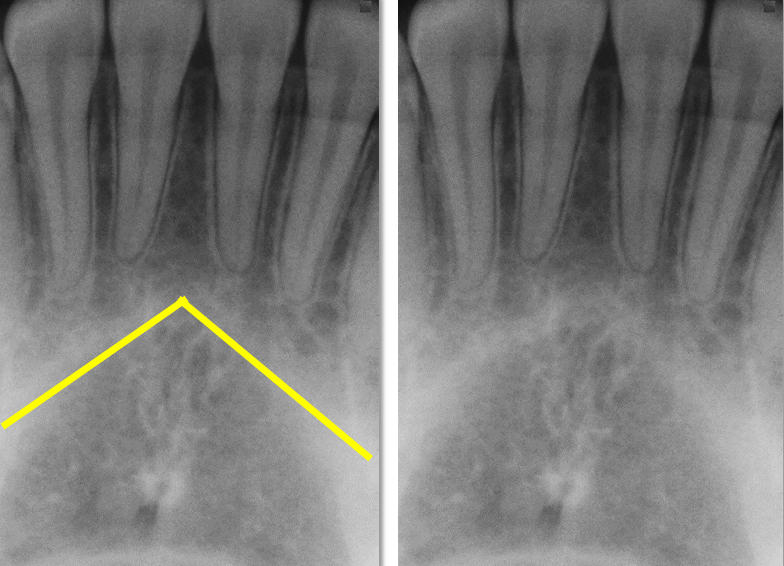

what is this, its description and its appearance on images

anterior nasal spine

sharp projection of maxilla located at anterior inferior portion of nasal cavity and septum

v shaped radiopaque area located at the intersection of floor nasal cav and septum, may be seen

nasal cavity

pear shaped compartment of bone located superior to maxilla

v shaped radiolucent area superior to maxillary incisors, may be seen